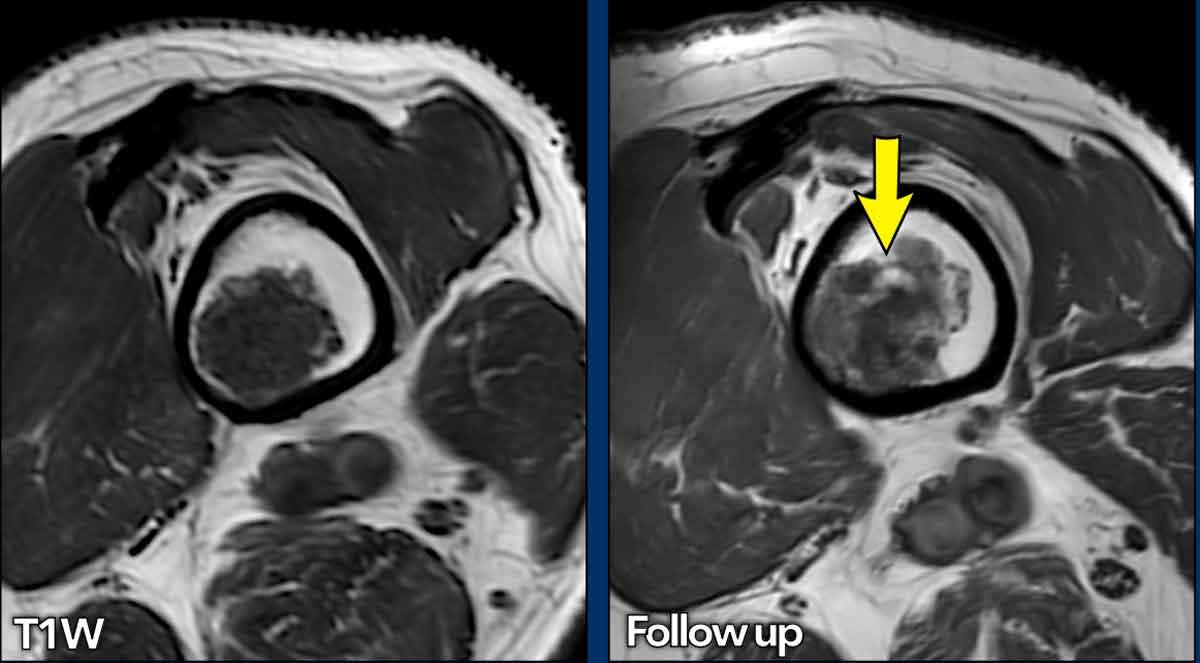

Mỡ xen kẽ

Các nốt sụn có thể có tủy mỡ xen kẽ giữa chúng, còn gọi là mỡ xen kẽ (interspersed fat) hoặc mỡ bị nhốt (entrapped fat).

Điều này được đánh giá tốt nhất trên

hình ảnh T1-weighted và xuất hiện trong các tổn thương ở phía lành tính của

phổ bệnh, tức là trong các ACT.

Ví dụ, trong quá trình theo dõi

các ACT, lượng mỡ xen kẽ và vôi hóa có thể tăng lên,

điều này có thể được hiểu là sự “trưởng thành” của tổn thương.

Điều này thậm chí

có thể gây ra sự giảm kích thước của khối u theo thời gian.

Cả sự trưởng thành mỡ và

tăng vôi hóa của khối u sụn theo thời gian đều là dấu hiệu của tính lành tính.

Trường hợp này đã được trình bày trước đây.

Nhìn lại hình ảnh MRI trước đó được thực hiện 5 năm trước, tổn thương đã tăng trưởng 6 mm theo chiều sọ-đuôi.

Cũng lưu ý sự mở rộng của tổn thương về phía trước (mũi tên vàng).

Không có hiện tượng mỏng vỏ xương, phù tủy xương hay viêm màng xương.

This lesion is an

ACT and remains in follow-up.